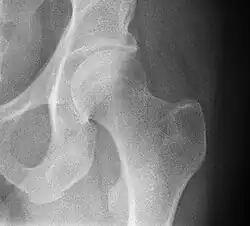

In vertebrate anatomy, the hip, or coxa[1] (pl.: coxae) in medical terminology, refers to either an anatomical region or a joint on the outer (lateral) side of the pelvis.

The hip region is located lateral and anterior to the gluteal region, inferior to the iliac crest, and lateral to the obturator foramen, with muscle tendons and soft tissues overlying the greater trochanter of the femur.[2] In adults, the three pelvic bones (ilium, ischium and pubis) have fused into one hip bone, which forms the superomedial/deep wall of the hip region.

The hip joint, scientifically referred to as the acetabulofemoral joint (art. coxae), is the ball-and-socket joint between the pelvic acetabulum and the femoral head. Its primary function is to support the weight of the torso in both static (e.g. standing) and dynamic (e.g. walking or running) postures. The hip joints have very important roles in retaining balance, and for maintaining the pelvic inclination angle.

Articulation

The hip joint or coxofemoral joint[5][6] is a ball and socket synovial joint formed by the articulation of the rounded head of the femur and the cup-like acetabulum of the pelvis.[7] The socket of the acetabulum is pointing downwards and anterolaterally. The socket is also turned such that the outer edge of its roof is more lateral than outer edge of the floor.[7] It forms the primary connection between the bones of the lower limb and the axial skeleton of the trunk and pelvis. Both joint surfaces are covered with a strong but lubricated layer called articular hyaline cartilage.

The cuplike acetabulum forms at the union of three pelvic bones — the ilium, pubis, and ischium.[8] The Y-shaped growth plate that separates them, the triradiate cartilage, is fused definitively at ages 14–16.[9] It is a special type of spheroidal or ball and socket joint where the roughly spherical femoral head is largely contained within the acetabulum and has an average radius of curvature of 2.5 cm.[10] The acetabulum grasps almost half the femoral ball, a grip deepened by a ring-shaped fibrocartilaginous lip, the acetabular labrum, which extends the joint beyond the equator.[8] The centre of the acetabulum (fovea) does not articulate to anything. Instead, it is lined with fat pad and attached to ligamentum teres. The acetabular labrum is horse-shoe shaped. Its inferior notch is bridged by transverse acetabular ligament.[7] The joint space between the femoral head and the superior acetabulum is normally between 2 and 7 mm.[11]